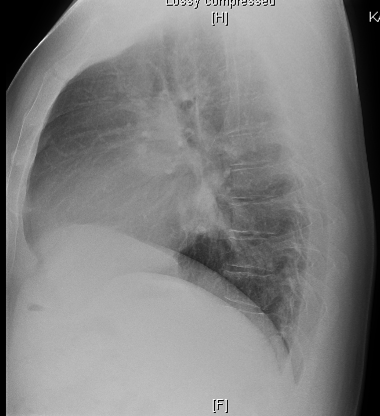

Chest X-Ray